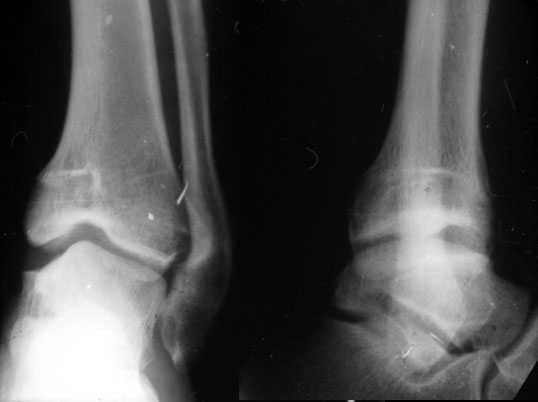

Аппаратом можно сделать все минимально инвазивно и травматично, вырастить клиновидный регенерат после чрескожной остеотомии через один или два разреза 0,5 см. В приложении похожий по локализации случай, только более давние последствия травмы с замыканием части зоны роста, деформация побольше, плюс укорочение голени было.

Уважаемый Александр то что вы показали это интересно, но это два разных случая. В ваших снимках большая деформация, которая требует выращивания массивного регенерата, поэтому здесь согласен лучше аппарат, а представленном случае дефект будет небольшой поэтому накостный синтез решит все проблемы за 2 недели без ключей 8*10 в течении 3-5 месяцев.Зачем себе создавать головную боль.

Согласен, тут деформация меньше, но все-таки заметная, почти 20 градусов. Я бы устранял ее как на приложенной картинке.

При таком варианте с аппаратом все легко и просто. С пластиной - должны быть трудности. Может быть, следовало бы планировать коррекцию как-то иначе? Как?